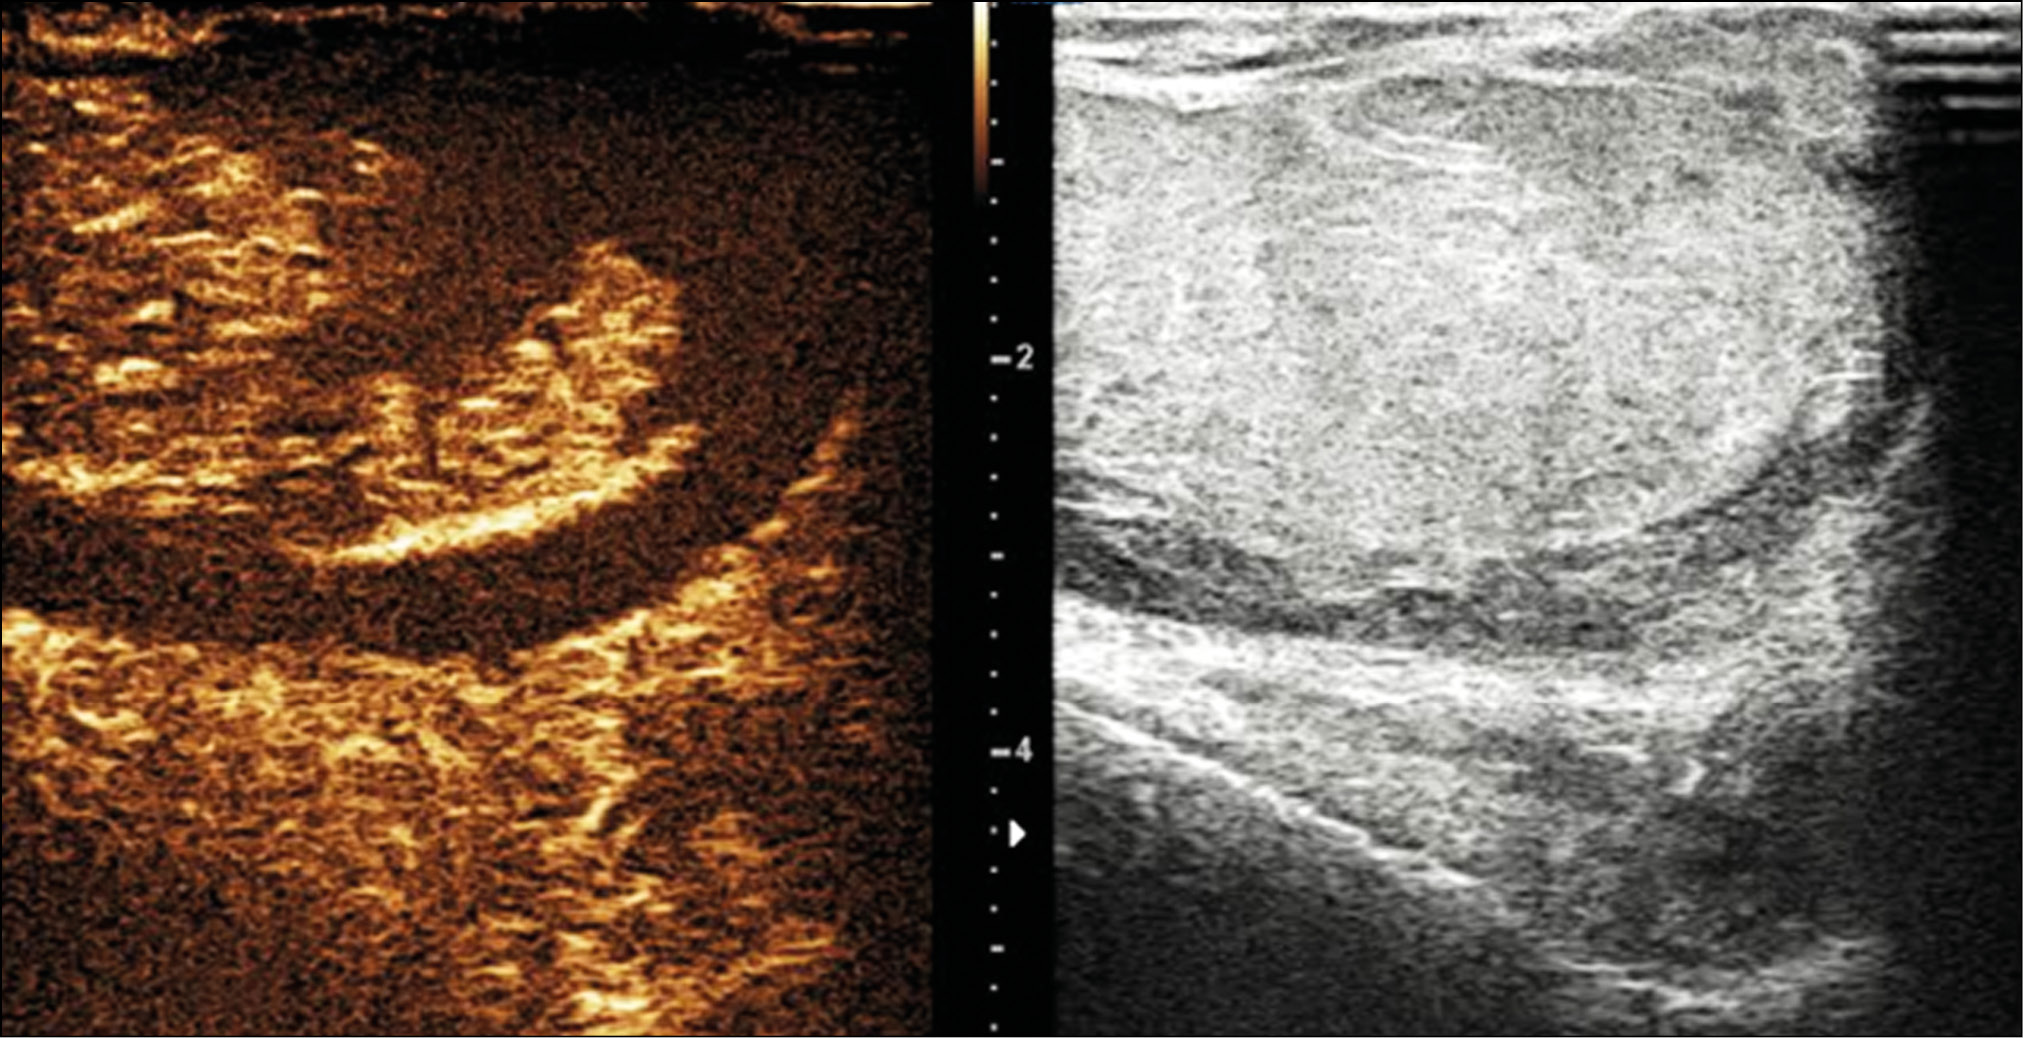

A healthy 15-year-old male teen was hit in the scrotum with a kick in the groin during a football match. He had an immediate and severe pain. After a few hours, although symptoms had improved, he presented to our emergency department with persistent swelling and purplish discoloration of the left scrotum. He did not report any other injuries. The genitourinary examination revealed that the left hemiscrotum was about two times larger than the right with severe ecchymosis. The left testicle was difficult to palpate because of pain and swelling, whereas the right testicle had a normal size and did not reveal any palpable abnormalities. The cremasteric reflex was not elicited on the left side. Scrotal ultrasonography (US) showed moderate scrotal edema and hematocele with a discontinuity in the tunica albuginea characterized by an abnormal contour (Figure 1). Color Doppler US (CDUS) documented a loss of vascularization in the upper pole that extruded into the broken portion of the testicle of approximately 2.5 cm (Figure 2) but no evidence of torsion or infarction. Urology consultation was requested, and a contrast-enhanced US (CEUS) was performed, which confirmed the diagnosis of testicular rupture and determined the amount of the vital parenchyma (Figure 3). The patient was hospitalized for urgent examination of the left hemiscotum based on the US results. During surgery, a large hematocele was evacuated, and a closer inspection of the testicle revealed a lesion of the tunica albuginea. Primary closure of the tunica was performed (Figure 4). The patient made an uneventful recovery, and he was discharged after 4 days.

Figure 1. B-mode ultrasonography images. (a) Interruption of the tunica albuginea with the protrusion of echogenic material (arrow) that represents an index of breaking. (b) Hematocele of moderate size (arrow) and a heterogeneous appearance of testicular parenchyma, attributable to an intratesticular contusion.